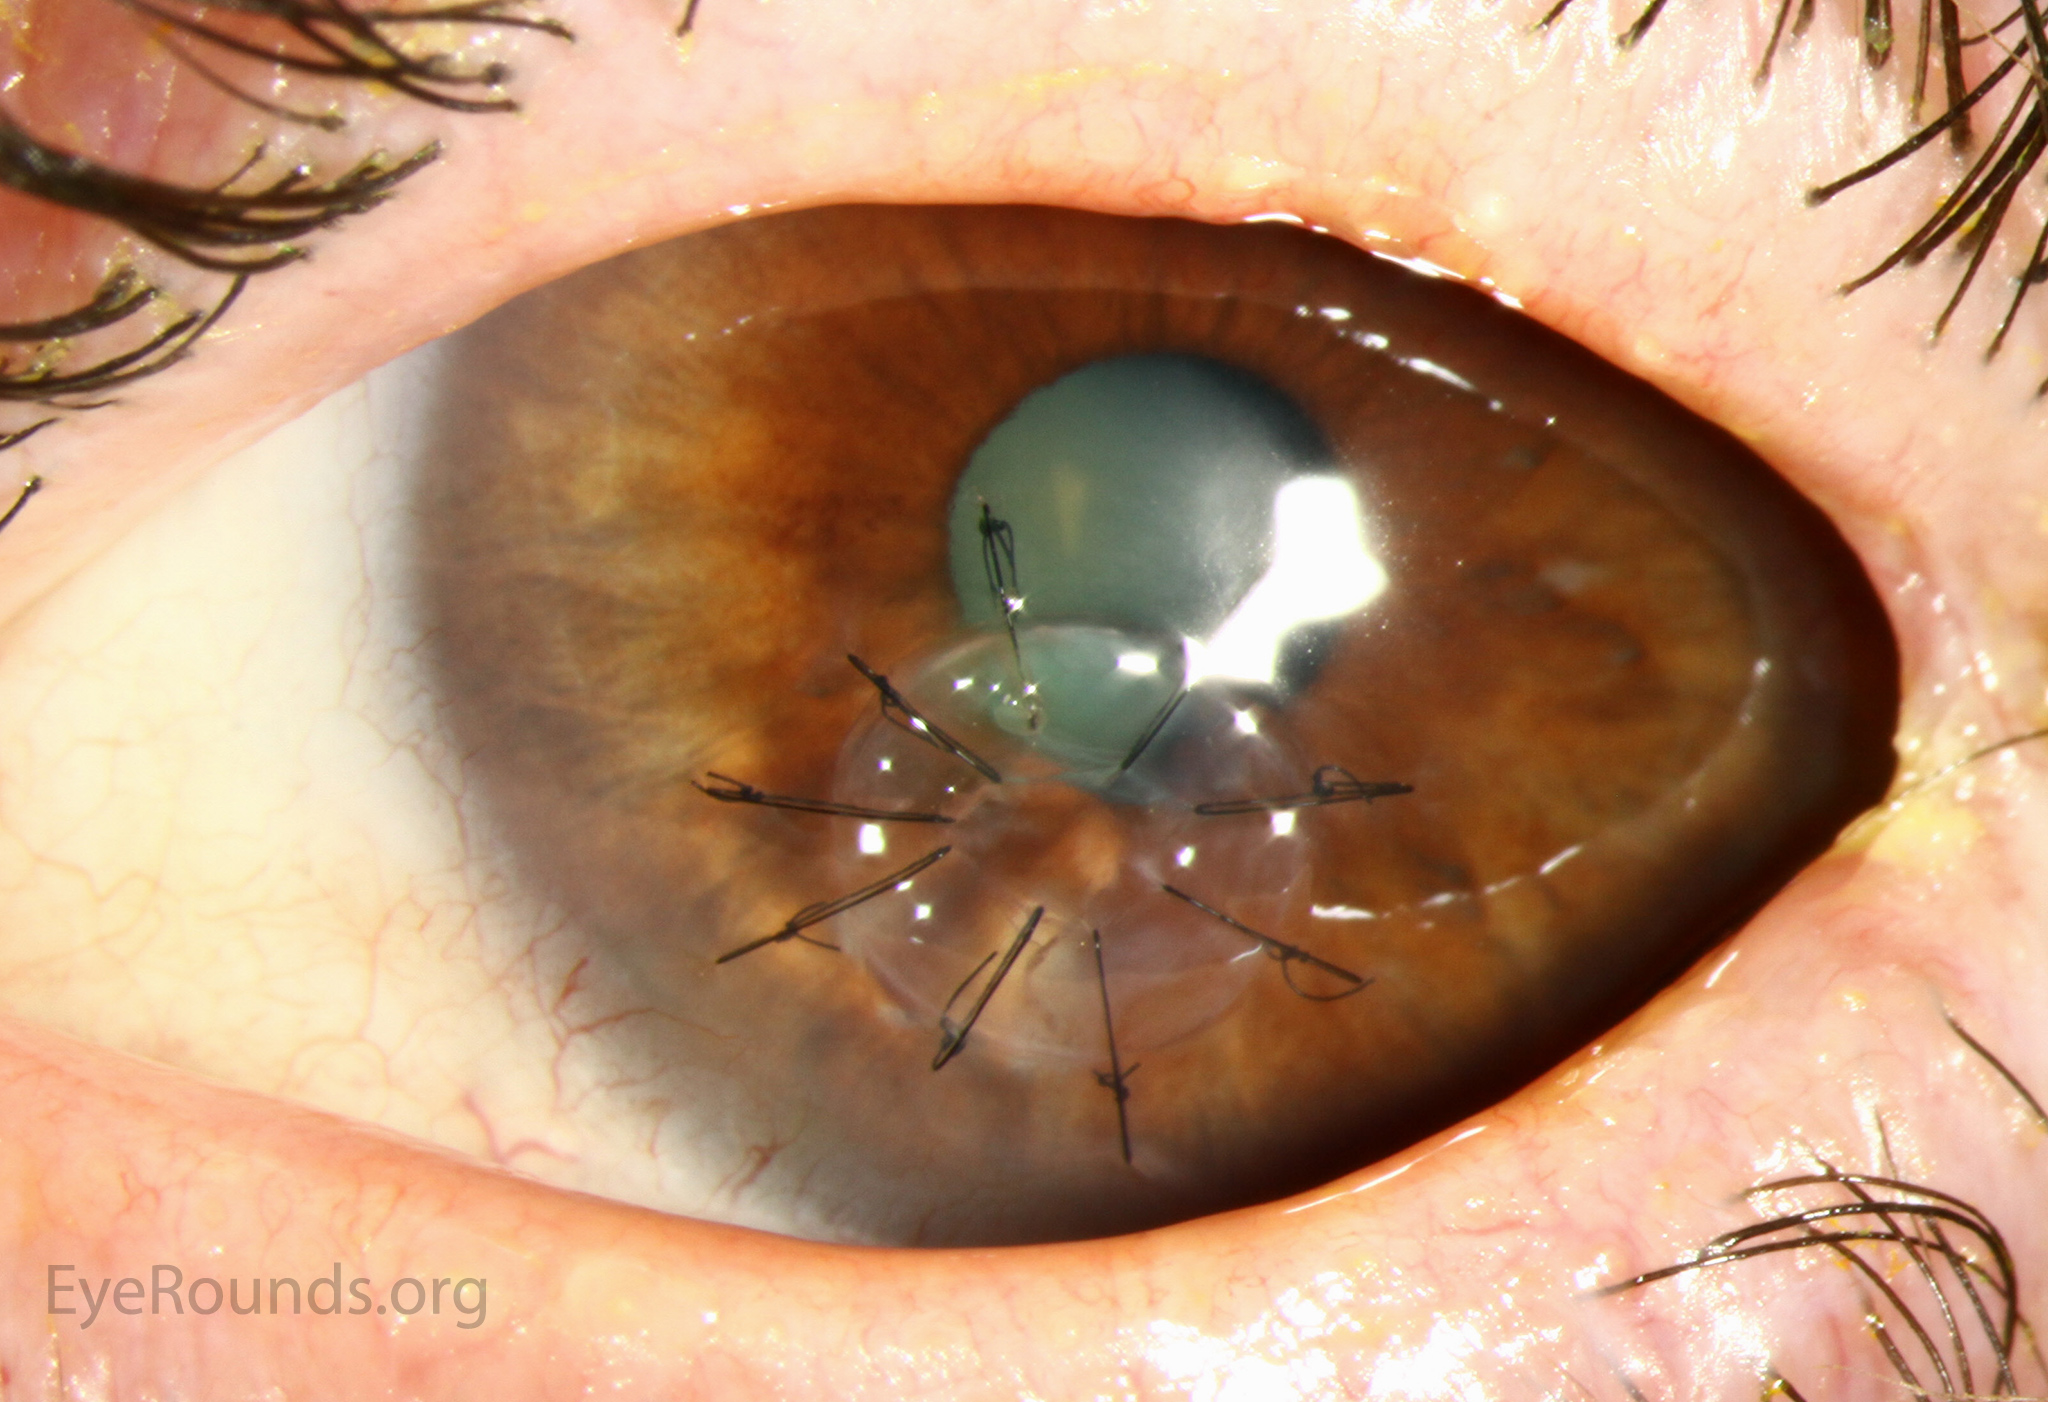

DALK is a partial-thickness cornea transplant procedure that involves selective transplantation of the corneal stroma, leaving the native Descemet membrane and endothelium in place. A trephine of an appropriate diameter is used to make a partial-thickness incision into the patient's cornea, followed by pneumodissection or manual dissection of the anterior stroma. This is followed by placement of a graft prepared from a full-thickness punch in which the donor endothelium-Descemet membrane complex has been removed. The intention is to preserve the patient's Descemet membrane and endothelium. Similar to PK, the graft is secured with interrupted and/or running sutures (Figure 5) and these are then selectively removed post-operatively (Figure 6).